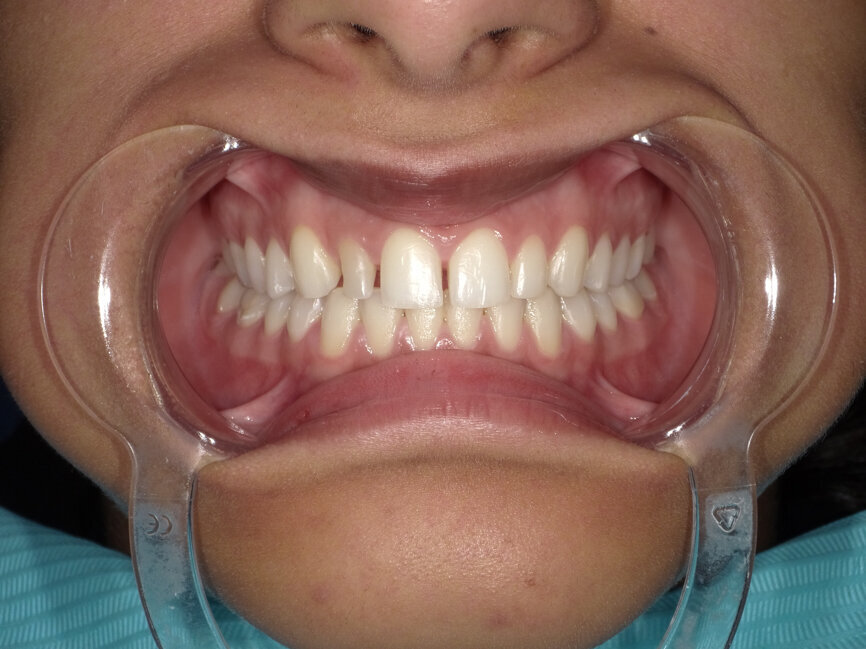

After the treatment planning discussion, the patient requested to proceed with direct resin-bonded composite veneers to enhance her smile. After the old composite fillings were removed (Fig 3, 4), smile design, was done to restore the golden proportion by modifying the shape and size of the teeth. Based on the smile design a mock-up was created to help obtain patient approval on the expected outcome and fabricate the silicone index.

Fig 3: Smile after removal of old restorations